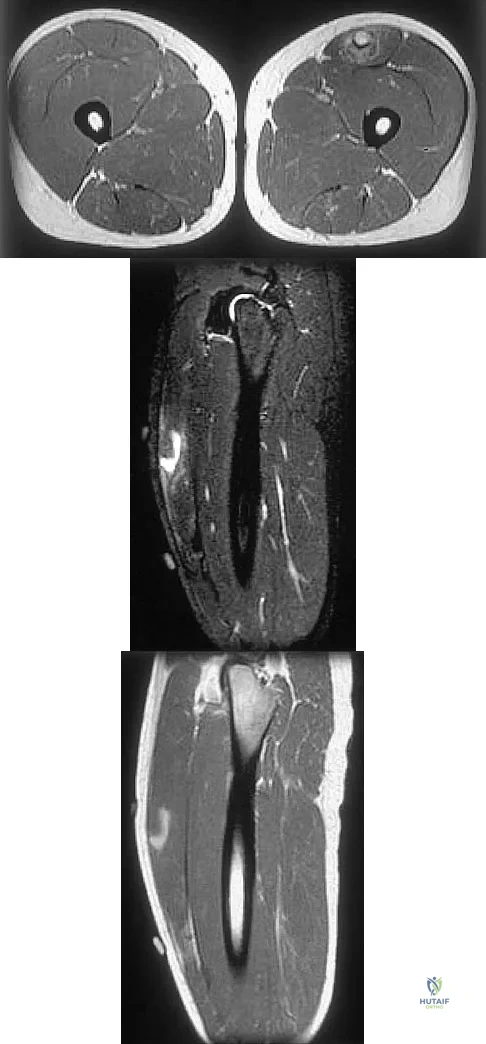

Question 50

Figures 34a through 34c show an axial proton density (spin echo long TR, short TE) image, a sagittal inversion recovery (STIR) image, and a sagittal T1-weighted (short TR, short TE) image of the left thigh. What is the most likely diagnosis?

Explanation